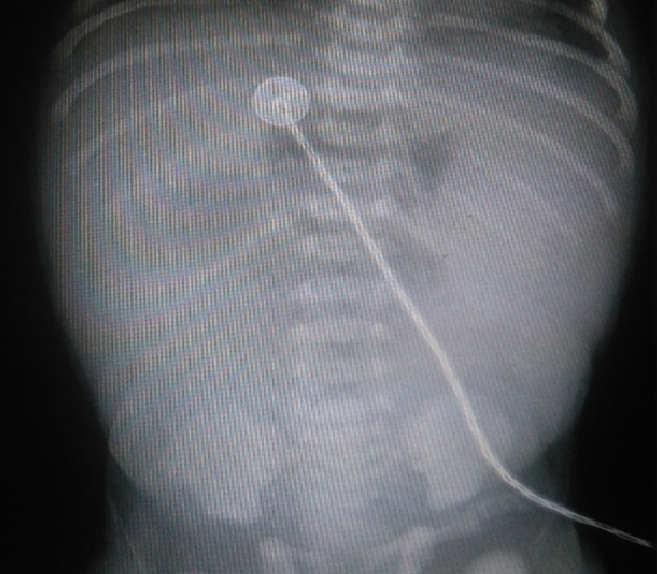

Al examen físico lo que más llamó la atención abdomen globuloso tenso con resistencia a la palpación. Se le realizó una radiografía abdominal en la que se observó una imagen de triple burbuja. No se apreció aire en la ampolla rectal, como se puede valorar en la siguiente imagen (figura 1).

Figura 1. Radiografía abdominal en la que se observa una imagen de triple burbuja: No se aprecia aire en la ampolla recta.